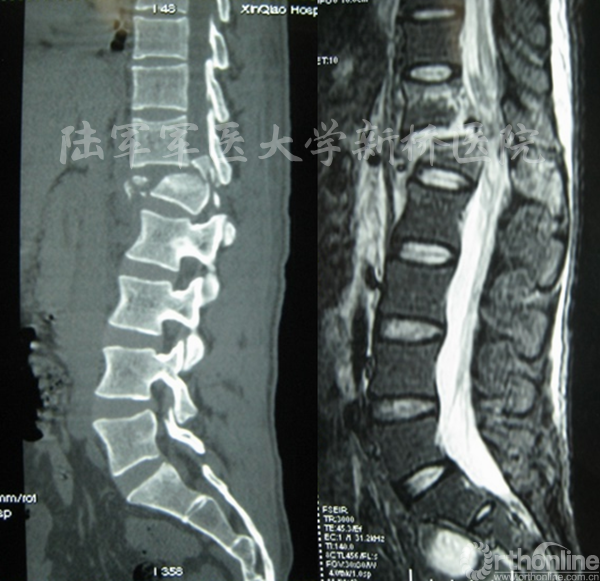

②脊柱爆裂性骨折伴有不稳者(术前CT平扫证实骨折未累及椎体后缘或累及椎体后缘但椎管占位小于30%,MRI示后纵韧带完整,无需行椎管减压或探查者);

Zhang W, LI HY, Zhou Y, et al. Spine 2016,41(19B):23-29.